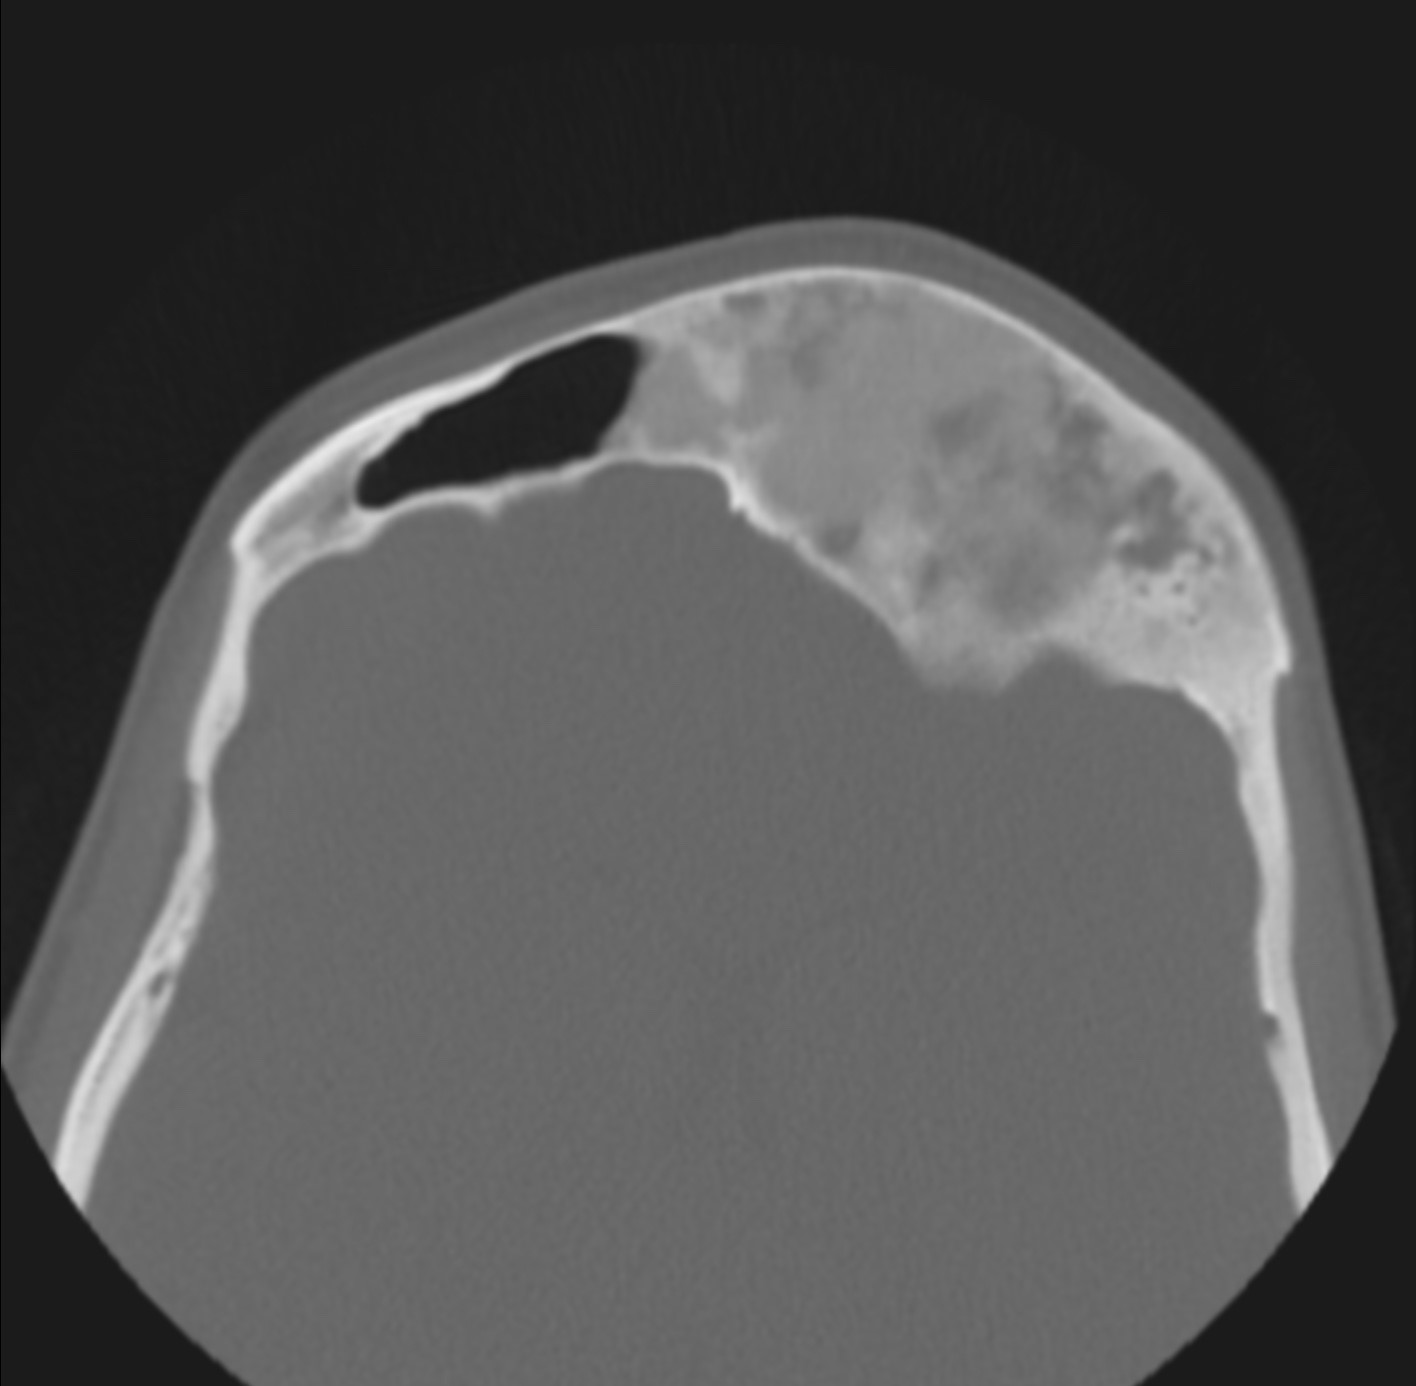

1. Resección Tumoral: Este procedimiento implica la extirpación del tumor. Los cirujanos utilizan técnicas precisas para eliminar el tumor sin dañar estructuras circundantes críticas, como nervios, vasos sanguíneos y tejidos adyacentes. (Imagen 1 y 2)

Imagen 1 y 2: Tomografía de cara. Se evidencia masa tumoral extensa con compromiso del hueso frontal y etmoides, ocasionando compresión cerebral y del globo ocular, así como asimetría facial. El tratamiento quirúrgico implicó resección tumoral y reconstrucción craneofacial con biomodelo tridimensional.